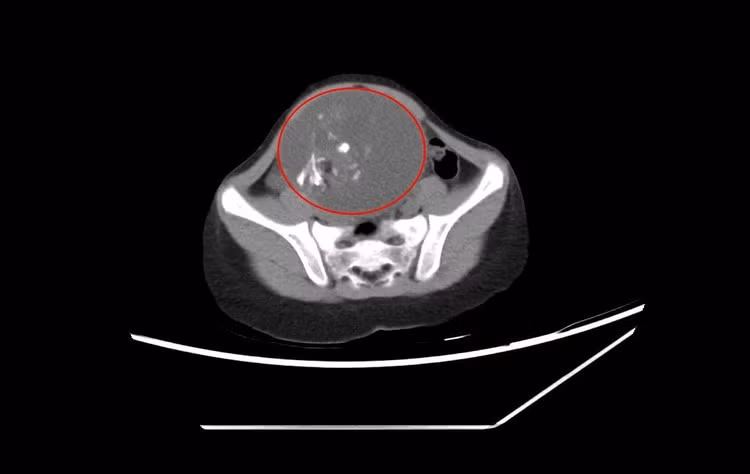

Bệnh viện Đa khoa tỉnh Quảng Ninh cũng vừa bóc tách khối u quái thành công cho bệnh nhi T.N (6 tuổi) ở TP Hạ Long. Theo gia đình, N. ở nhà thường xuyên táo bón, khó đại tiện, thỉnh thoảng thấy bụng có khối cứng khi đói nên đưa đến Bệnh viện Đa khoa tỉnh thăm khám. Kết quả, bệnh nhi khối u buồng trứng 10cm.

u-quai-10cm.jpg

Hình ảnh khối u quái buồng trứng 10 cm trên phim chụp – Ảnh BVCC